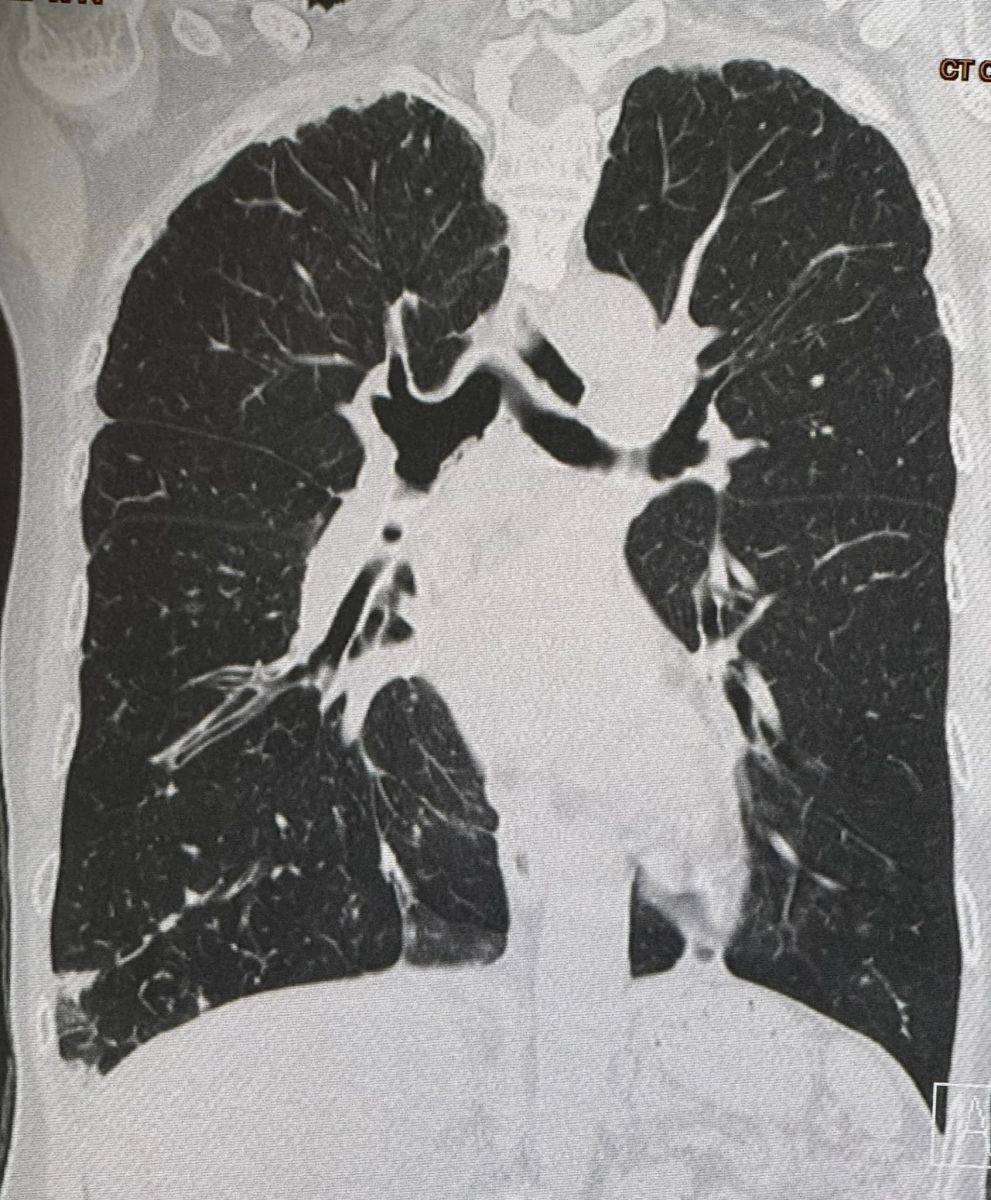

จากการตรวจร่างกาย ฟังปอดมีเสียงผิดปกติทั้ง 2 ข้าง เอกซเรย์ปอดผิดปกติเข้าได้กับหลอดลมโป่งพองทั้ง 2 ข้าง (ดูรูป) ทำคอมพิวเตอร์ปอดเห็นหลอดลมโป่งพองในปอดทั้ง 2 ข้าง (ดูรูป) ส่งเสมหะย้อมเชื้อหาวัณโรค AFB smear ให้ผลบวก วินิจฉัย: โรคหลอดลมโป่งพอง สงสัยติดเชื้อวัณโรค หรือวัณโรคเทียม จึงให้ยา INH,rifampicin,ethambutol รักษาวัณโรค ร่วมกับ azithromycin รักษาวัณโรคเทียม 2 สัปดาห์ หลังกินยาดีขึ้น หยุดไอ ไม่มีเสมหะ ผลเพาะเชื้อขึ้นเชื้อวัณโรคเทียม 3 ชนิด คือ M.fortuitum, M. intracellulare และ M. gordonae เมื่อทราบผลเพาะเชื้อได้หยุดยาทุกชนิดก่อน ขอเก็บเสมหะอีกครั้งแต่เก็บไม่ได้ เพราะไม่มีเสมหะ แนะนำให้หยุดการเทปุ๋ยรอบต้นไม้ในสวน